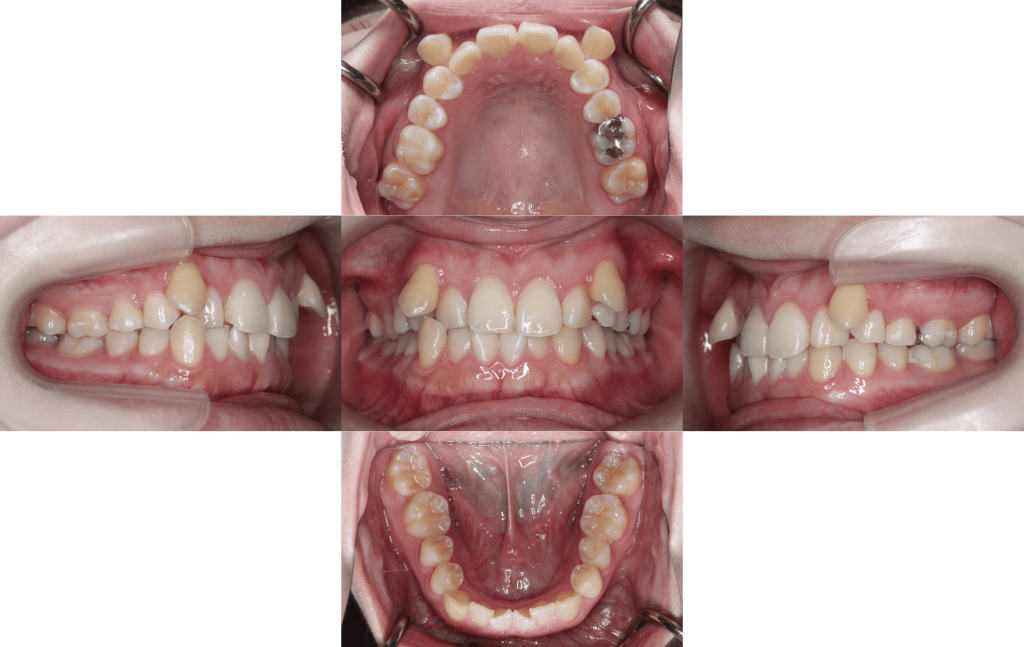

八重歯のでっぱりを治したい(治療期間6か月/治療回数8回)

Before

After

約6か月経過

年齢層

20代

性別

女性

主訴

・八重歯のでっぱり・3⏇3凸凹・正中線のズレ

治療費用

¥1,287,000

治療期間

6か月(治療中)

抜歯

上顎両側第一小臼歯

矯正の装置

裏側矯正(舌側矯正)

副作用、リスク

歯肉退縮,歯根吸収,疼痛,咬合の違和感,装置の違和感,虫歯,歯肉炎